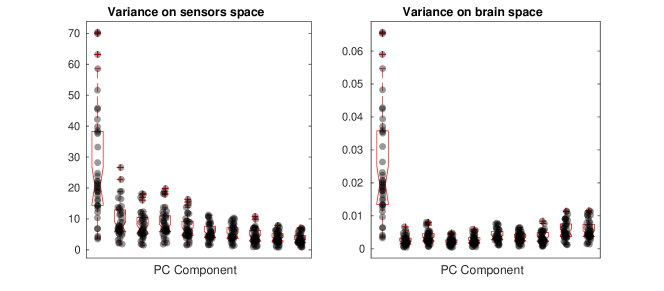

The second part of the analysis focuses on applying the proposed methodology to a multi-subject setting. Specifically, different subjects are considered. For each subject, the 6 minutes scan is used to compute a covariance matrix, resulting in covariance matrices . The template geometry in Figure 10 is used as a model of the brain space. Algorithm 2 is then applied to find the PC covariance functions on the template brain, associated with . We run the algorithm for iterations, and choose the regularizing parameter to be by inspecting the L-curve plot in the right panel of Figure B.2. The results for are shown in the appendices. The energy maps of the estimated functions , and and the associated first three covariance functions , and , are shown in Figure 13. High intensity areas, in yellow, indicate which areas present high average connectivity. In Figure 14, we show the subject-specific associated variances, both in the sensors space and the brain space.

The presented methodology opens up the possibility to understand population level variation in functional connectivity, and indeed, whether, just as we need different forward operators for individuals (due to anatomical differences), we should also be considering both population and subject-specific connectivity maps when analyzing connectivity networks. In fact, it is of interest to note that in both the single and multi-subject settings, the areas with high interconnectivity, displayed in yellow in Figure 11 and 13, seem to be at least partially overlapping with the brain’s default network (Buckner et al., 2008; Yeo et al., 2011). The brain’s default network consists of the brain regions known to have highly correlated hemodynamic activity (i.e. highest functional connectivity levels), and to be most active, when the subject is not performing any specific task. An image of the spatial configuration of the default network can be found, for instance, in Figure 2 of Buckner et al. (2008). From the plots of the associated variances in the sensors space (left panel of Figure 12 and Figure 14) we can see that these areas are also the ones that show high variability in connectivity across time or across subjects. This might suggest that the brain’s default network is also the brain region that shows among the highest levels of spontaneous variability in connectivity.

The plots of the variances on the brain space (right panel of Figure 14), when compared to those on the sensors space (left panel of Figure 14), demonstrate that these type of studies are highly sensitive to the choice of the regularization, not only in terms of spatial configuration of the results, but also in terms of estimated variances on the brain space. With a naive ‘first reconstruct and then analyze’ approach, where the reconstructed data on the brain space replace those observed on the sensors space, this issue could go unnoticed, as the variability that does not fit the chosen model is implicitly discarded in the reconstruction step and does not appear in the subsequent analysis. Also, importantly, our analysis deals with statistical samples that are entire covariances, overcoming the limitations of seed-based approaches, where prior spatial information is required to choose the seed. Seed locations are usually informed by fMRI studies and this comes with the risk of biasing the analysis when comparing electrophysiological networks (MEG) and hemodynamic networks (fMRI).